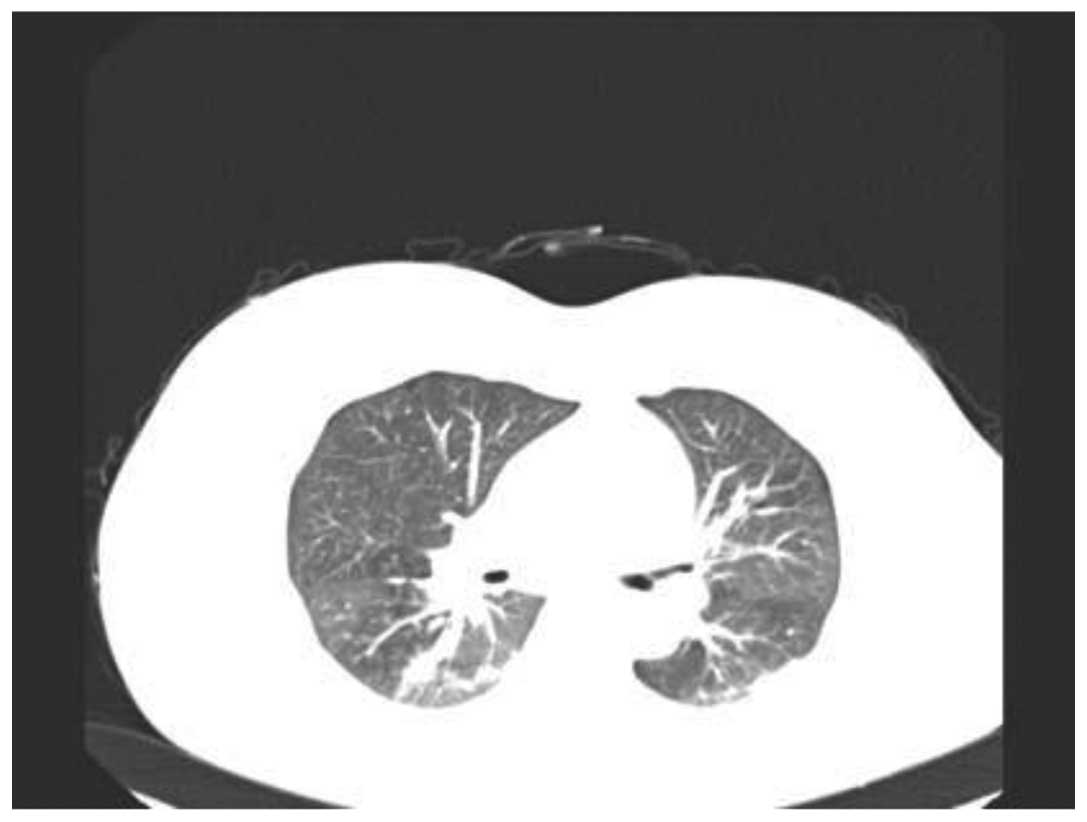

The present report describes two cases of paraquat poisoning by skin absorption. The cases involved contractual workers who were spraying paraquat in an orchard. Whilst spraying, some solution adhered to their skin. The skin developed erythema followed by blistering and hemorrhaging hemorrhagic diabrosis. Six days later the patients were admitted to the Department of Poisoning and Occupational Disease, Qilu Hospital of Shandong University (Jinan, China) with 3 and 2% total body surface area (TBSA) burns, respectively. Surgical debridement was performed and immunosuppressants were administered during the patients' treatment. The patients were treated successfully and had made a complete recovery following 21 days. From these cases it was examined how paraquat may cause skin injuries and occasionally poisoning. To the best of our knowledge, cases of paraquat poisoning are rare in China. A review of the relevant literature was performed.

Figure 1

Figure 2

Figure 3